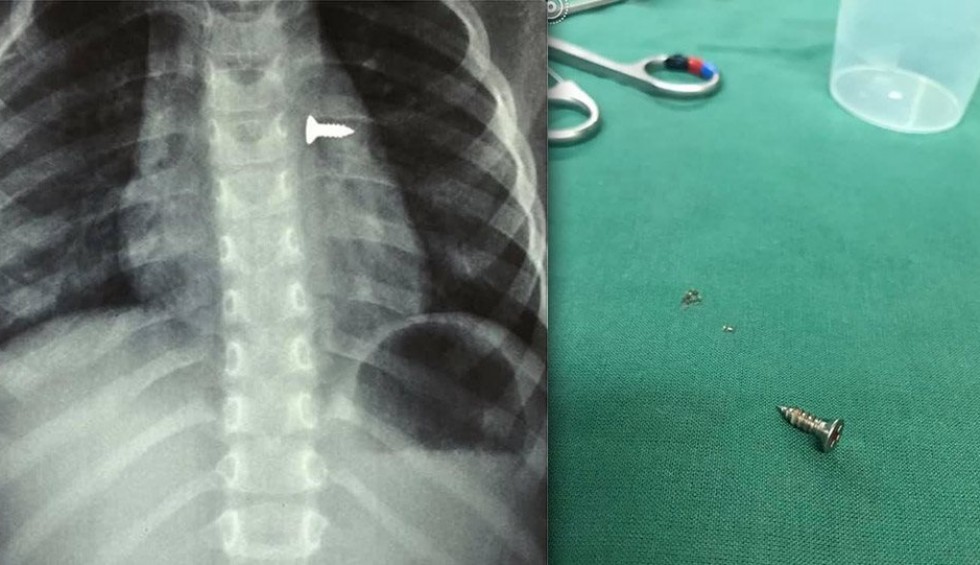

Κρήτη: Τρίχρονο κοριτσάκι κατάπιε βίδα που κατέληξε στον πνεύμονά του